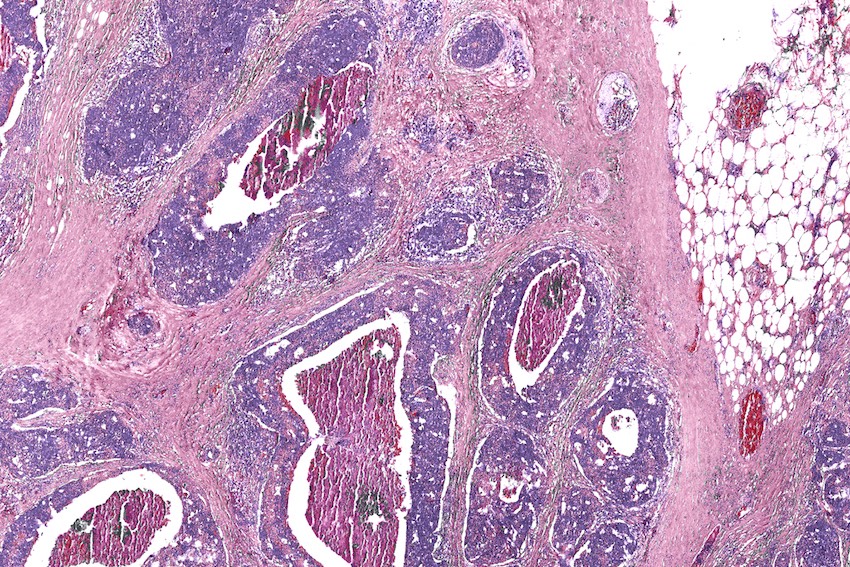

Adding infrared capability to a standard optical microscope enables digital biopsies – computational staining without adding any actual dyes or chemicals to the tissue sample. Credit: Rohit Bhargava/UIUC.